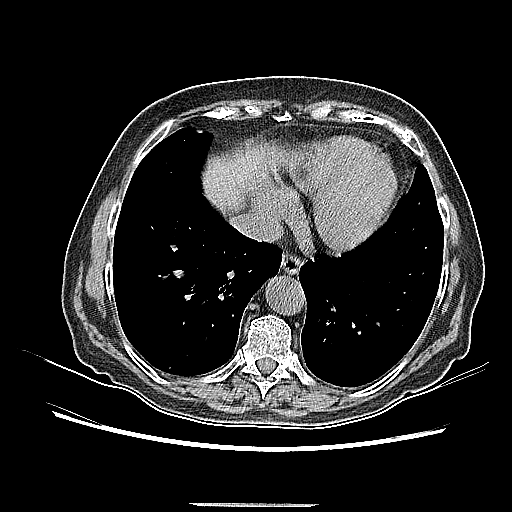

Original NATIVE CT scan (input)

Full window (WL 1023.5, WW 4095 β†’ Low βˆ’1024, High +3071)

Lung window (WL -600, WW 1500 β†’ Low βˆ’1350, High +150)

Mediastinum window (WL 40, WW 400 β†’ Low βˆ’160, High +240)